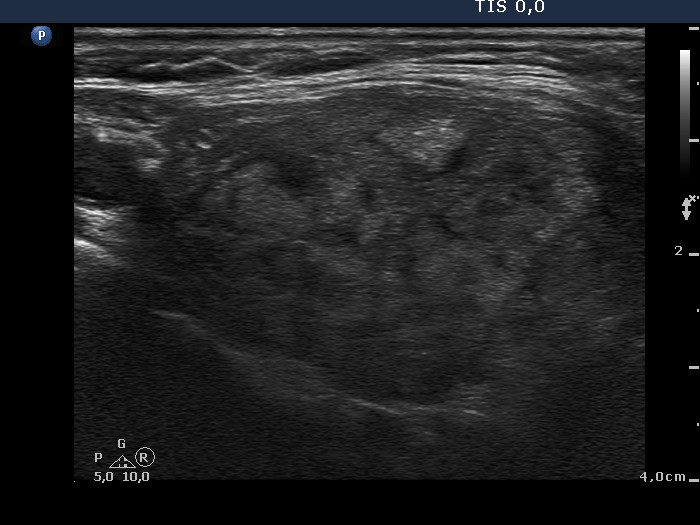

Follow-up investigation two years later (ultrasonographic picture 8)

Left lobe, another longitudinal scan. There is a hyperechogenic lesion in the ventral part of the lobe. It contains microcalcifications.